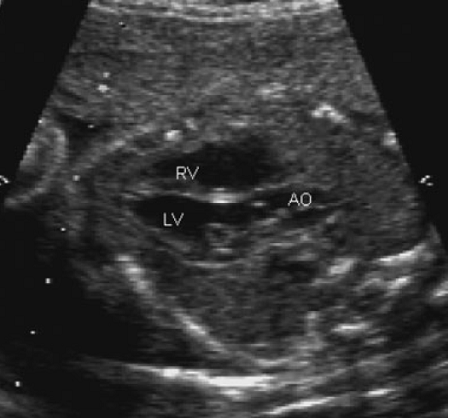

Nhờ việc sử dụng rộng rãi siêu âm thường qui trong sản khoa, mặt cắt 4 buồng tim được xem như một xét nghiệm tầm soát BTBS[7] (hình 1). Mặt cắt 4 buồng tim có một số đặc điểm là một xét nghiệm tầm soát tốt đối với BTBS. Nó là một phần trong khám nghiệm siêu âm cơ bản. Nó không đòi hỏi có kĩ năng siêu âm đặc biệt vì hình ảnh dễ thực hiện ở mặt cắt ngang ngực. Nó có thể ghi nhận được ở mọi tư thế thai nhi và đạt được hơn 95-98% ở thai sau 19 tuần trong lần khám đầu và mất 1-2 phút[24,90,96].

Hình 1. Mặt cắt 4 buồng

Một vài bệnh tim có mặt cắt 4 buồng bình thường. Đây cũng là hạn chế lớn nhất của việc sử dụng thường qui mặt cắt 4 buồng trong tầm soát BTBS. Bảng 2 liệt kê các bất thường tim mà có mặt cắt 4 buồng bình thường, bảng 3 liệt kê các bệnh tim có mặt cắt 4 buồng bất thường.